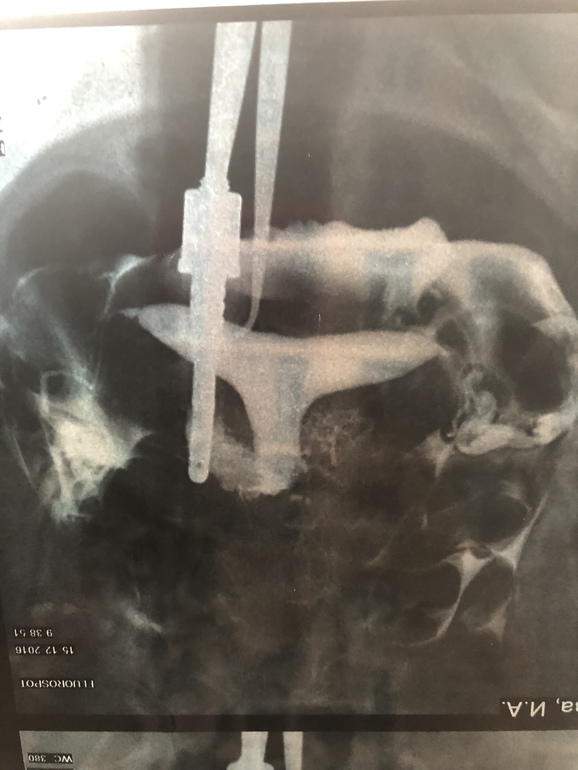

Сегодня была у врача в другой клинике, пришла на УЗИ, с полным перечнем документов и сказала, что хочу вторую попытку ВМИ. Врач посмотрел анализы, УЗИ, мрт и попросил снимок труб. По снимку сказал, у вас выход только один, ЭКО. Сказать, что я была в шоке, не сказать ничего. Ещё и муж уезжает надолго в командировку. У меня есть результат метросальпингографии в котором написано «заключение : полость матки седловидной формы, контуры четкие, ровные, отклонена кзади. Правая маточная труба визуализируеься на всём протяжении, несколько извитая, выход контраста свободный. Левая маточная труба визуализируется на всём протяжении, выход контраста свободный.»

Сказал что трубы сужены и через них не проходит яйцеклетка, ВМИ может только привести к внематочной беременности, и разрыву трубы. И выход только один, ЭКО.

Мои трубы смотрели огромное количество врачей, напротажении с декабря 2016 года и никто, ни один врач, не говорил что трубы слишком заужены. Столько времени утрачено...